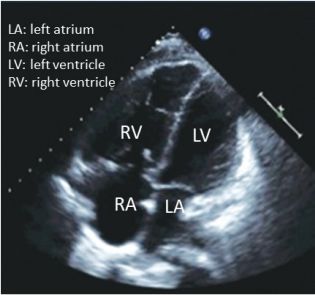

16. 有關肺動脈高壓的敘述,下列何者錯誤?

(A) 一氧化碳瀰漫量(Diffusing capacities of the lungs for carbon monoxide DLCO) 在肺動脈高壓患者會 下降 (B) 心臟超音波的影像(如附圖) (C) 在無睡眠呼吸障礙的肺動脈高壓患者,夜間缺氧(nocturnal desaturation)並不常見 (D) 肺動脈高壓患者均應接受抗核抗體 (antinuclear antibody),類風濕因子(rheumatoid factor),Scl 70抗體 (anti-scl-70 antibody)檢測 (E) 心音聽診時,第二心音肺動脈瓣成分會加重(accentuated P2)